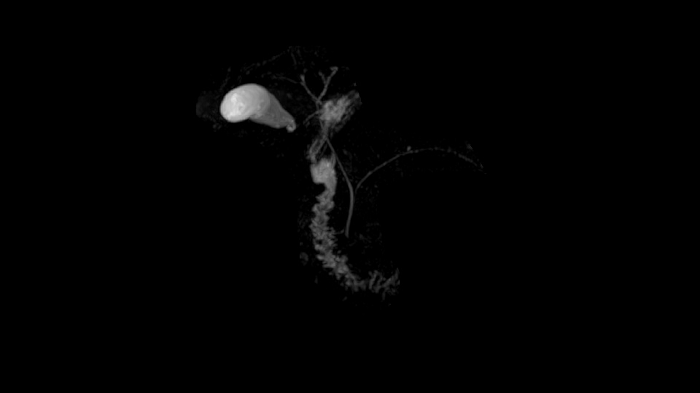

Abdomen

MRCP with Compressed Sensing

Abdominal imaging with T2w SPACE of the biliary ducts can be expedited with Compressed Sensing to reduce acquisition times. Both techniques offer high-resolution, high-quality MRCP for uncompromised abdominal investigation.

Compressed Sensing factor 6.5 | 1.2 x 1.2 x 1.0 mm3 | TA = 4:21 minutes

• Contour L Coil

• Spine Coil

80 cm bore MAGNETOM Free.Max

Image Courtesy: University Hospital Erlangen, Germany | Image-ID: 4aaaa0465